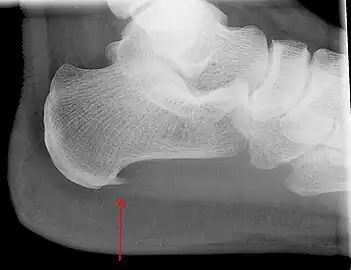

An incidental finding associated with this condition is a heel spur, a small bony calcification on the calcaneus (heel bone), which can be found in up to 50% of those with plantar fasciitis.[6] In such cases, it is the underlying plantar fasciitis that produces the heel pain, and not the spur itself.[13] The condition is responsible for the creation of the spur though the clinical significance of heel spurs in plantar fasciitis remains unclear.[12]

Heel bone with heel spur -

Medical imaging is not routinely needed. It is expensive and does not typically change how plantar fasciitis is managed.[15] When the diagnosis is not clinically apparent, lateral view X-rays of the ankle are the recommended imaging modality to assess for other causes of heel pain, such as stress fractures or bone spur development.[7]